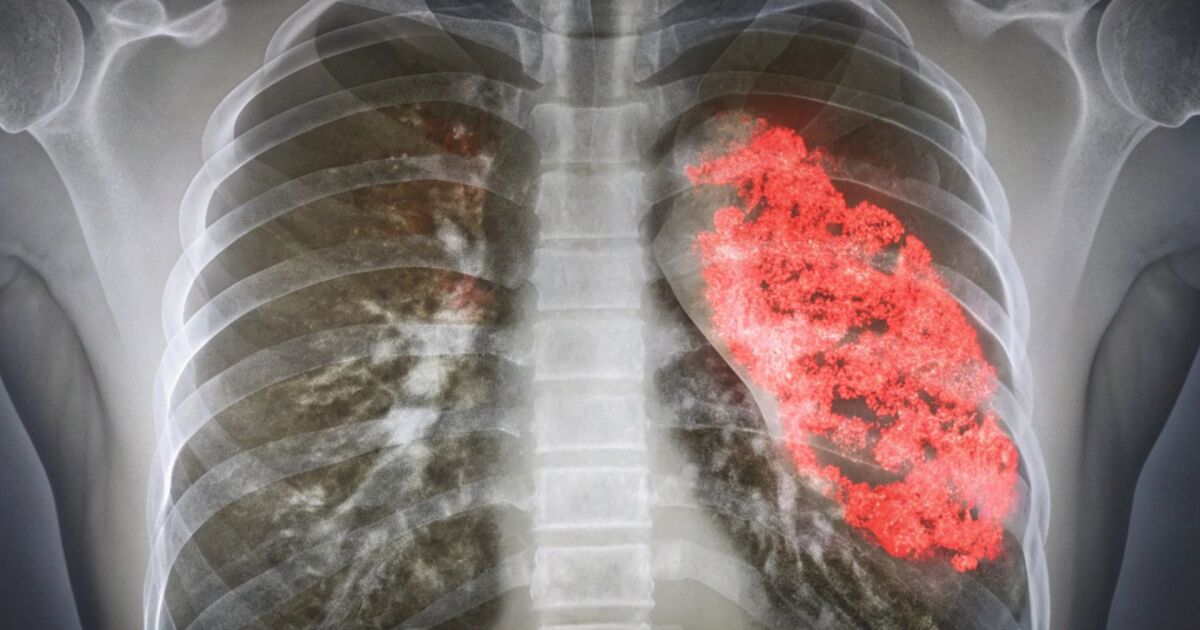

Пневмонията е белодробна инфекция, причинена от бактерии, вируси или гъбички. Когато патоген навлезе в белите дробове, алвеолите, малките въздушни торбички, отговорни за кислородния обмен, се запълват с течност. Това натрупване на течност причинява възпаление, което води до характерните симптоми на заболяването: кашлица, треска и затруднено дишане.

Кислороден дефицит: когато въздушните торбички се запълнят с течност, кислородът не може ефективно да достигне до кръвта. В резултат останалото тяло, включително жизненоважни органи като бъбреците, черният дроб и сърцето, губят кислород и не могат да функционират правилно. Липсата на кислород може да увреди тези органи трайно.